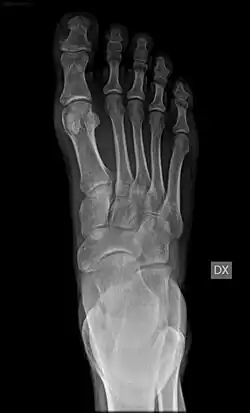

Radiografia metatarso

Em anatomia, denomina-se metatarso a parte mediana do , nos membros posteriores (ou extremidades inferiores,[1] no ser humano) dos mamíferos e outros vertebrados. É formado pelos cinco ossos metatarsais, que articulam com o tarso pelas suas extremidades proximais e com as primeiras falanges pelas extremidades distais.